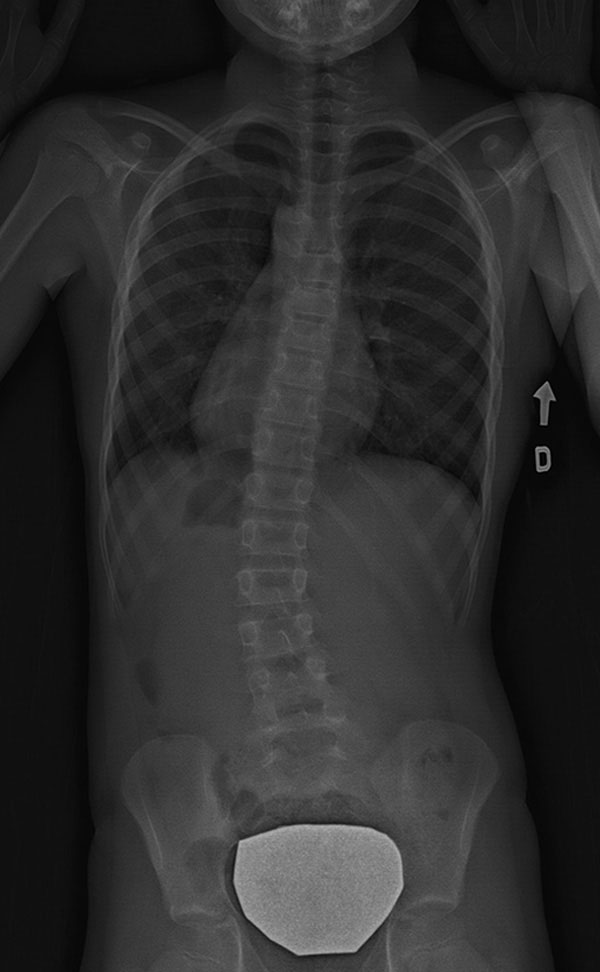

Scoliose lombaire – située au bas du dos

![]() |